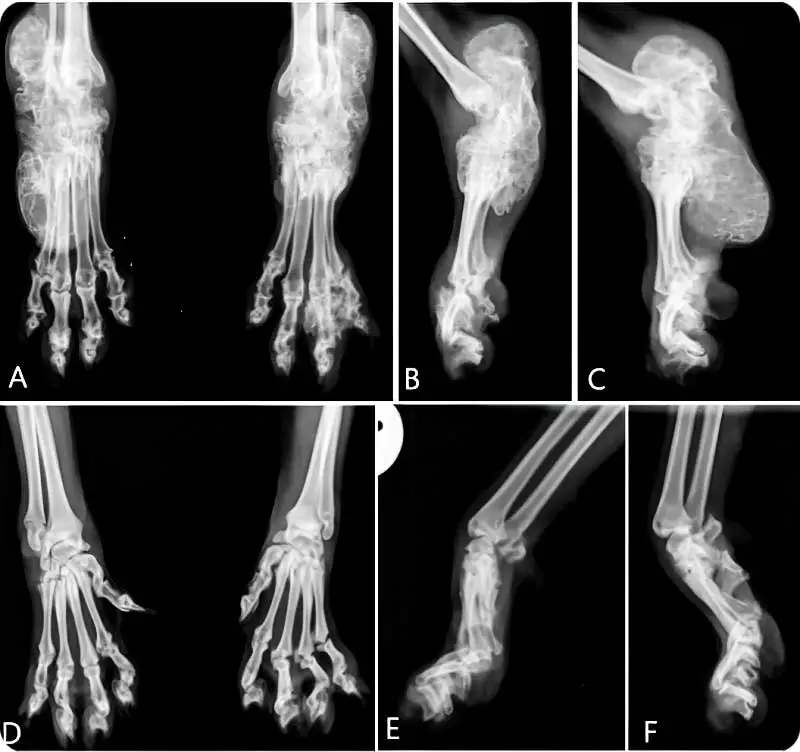

โรค Osteochondrodysplasia (OCD) หรือ โรคภาวะกระดูกเจริญผิดปกติของยีนหูพับ

แต่ถ้าการกลายพันธุ์แบบ mutation/mutation ก็จะมีอาการรุนแรงมากๆ เช่น กระดูกเท้า ขา กระดูกสันหลังผิดรูป ข้อเสื่อมรุนแรง ขยับตัวได้ลำบากและมีความเจ็บปวด

จริงๆแล้ว "ยีนหูพับ" นี้ มันไม่ได้ทำให้แค่หูเกิดการพับ หากพูดให้ชัดเจนและครอบคลุมก็คือ

เป็นยีนที่ทำให้กระดูกอ่อนของร่างกายเกิดการบิดงอ ผิดรูป ขาดการยืดหยุ่น ดังนั้นจุดที่เป็นกระดูกอ่อนและเห็นชัดที่สุดก็คือ "หู" ซึ่งในร่างกายนั้น ไม่ได้มีกระดูกอ่อนแค่ “หู” เท่านั้น

ยังมีส่วนอื่นๆในร่างกายอีกมากมาย ไม่ว่าจะเป็นตามข้อต่อต่างๆ หรือหมอนรองกระดูกสันหลังเป็นต้น

การมียีนหูพับตัวนี้อยู่จึงอาจมีการส่งผลกระทบต่อระบบต่างๆในร่างกายได้อีก ทางการแพทย์จึงเรียกว่า "โรคทางพันธุกรรม"